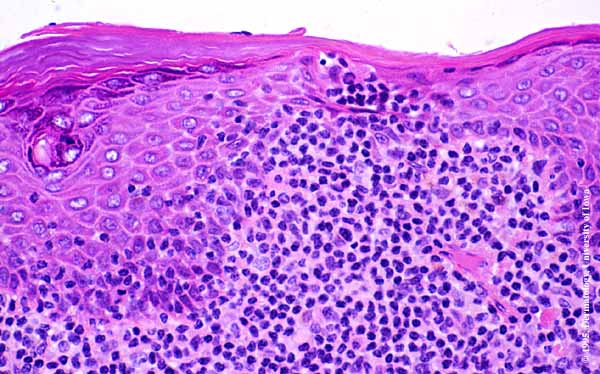

Mycosis Fongoïde =التفطر الكمئي